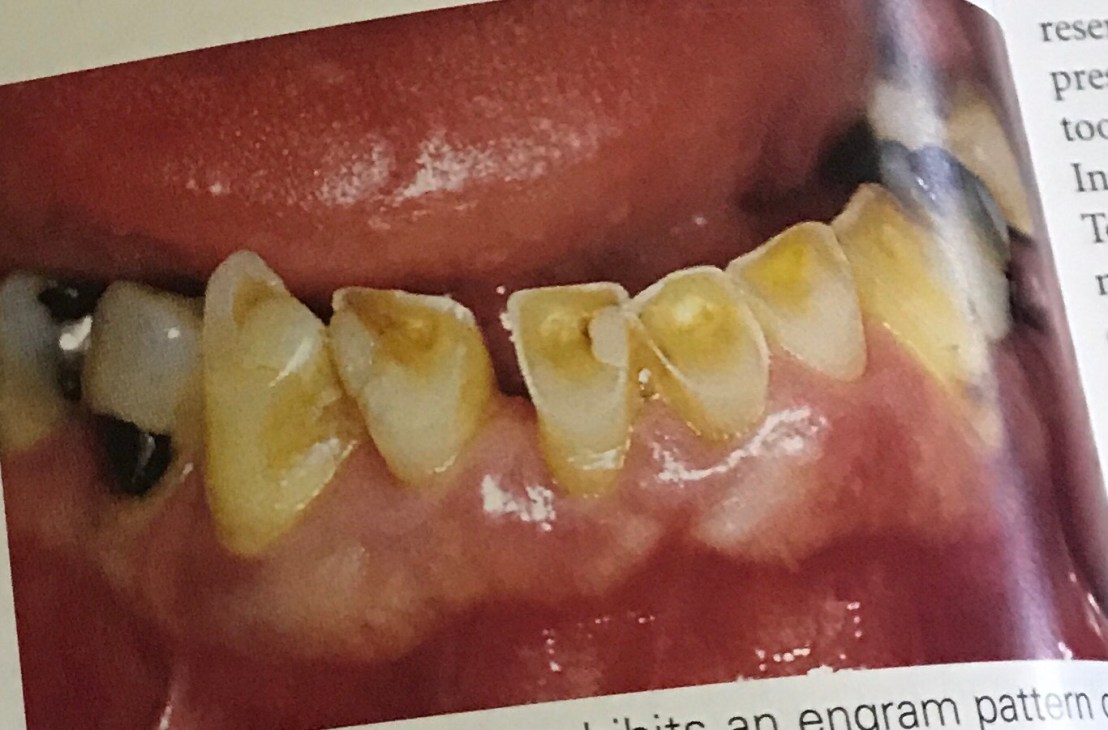

แสดงการสึกของ Canine ล่าง และ notch ที่ฟันคู่สบ 22 –> มี Bruxism

รูปล่าง เวลาทำ Working contact พบ Canine บนสบกับ 34 และสังเกตว่า คอฟันซี่ 34 เกิด abfraction–> แสดงถึง Parafunction

ดังนั้นเวลาที่เราต้องทำ Pros ในฟันหลัง จะต้องปรับแต่งการสบฟัน ไม่ให้เกิดลักษณะนี้ด้วย

ในคนไข้ที่มีฟันหน้าล่างสึก (Bruxism) แบบนี้ เราต้อง restore ฟันหน้าล่างขึ้นมาก่อน เพื่อให้เกิด Anterior guidance ที่ปกติ จึงจะสร้าง Prosthesis ในฟันหลังได้ (หมายความว่า ถ้าเราสร้าง Pros ขึ้นมาโดยไม่สนตำแหน่งฟันหน้า Pros จะ failure ไปด้วย)